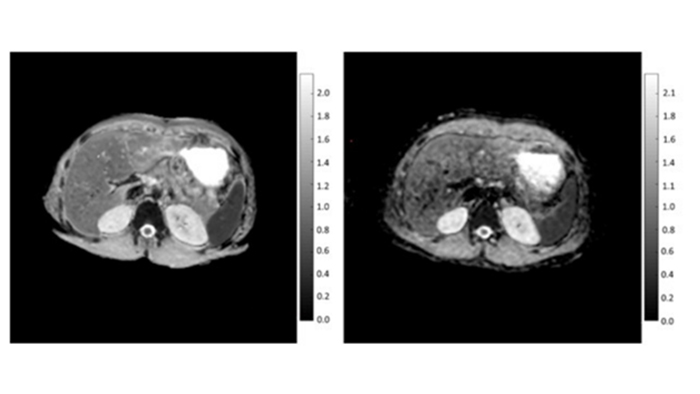

Рис. 1. Примеры ИКД(DWI) карт, полученных из DWI (слева) и DWIBS (справа) изображений. Значения измеряются ИКД в мм2/с. Изображение предоставлено сотрудниками медицинского радиологического научного центра им. А.Ф. Цыба.

Метастатическое поражение скелета встречается на фоне рака молочной железы и предстательной железы в 70–80% случаев аутопсий Более чем у половины онкопациентов отдалённое метастазирование начинается с поражения костей [2]. МРТ зарекомендовала себя эффективным методом В выявлении метастатического поражения скелета МРТ демонстрирует более высокие показатели чувствительности и специфичности (90,5 и 95% соответственно), чем сцинтиграфия (72,9 и 93,9%), и, по крайней мере, сопоставимыми ― с совмещённой ПЭТ-КТ с холином (89,7 и 96%) [3]. При этом, несомненно, помимо постановки первичного диагноза, интерес врачей рентгенологов заключается и в оценке ответа тех или иных злокачественных очагов на проводимое лечение, а также наблюдение их в динамике. Для этого одним из наилучших вариантов является количественная оценка ограничения диффузии (параметр ИКД, ADC). До этого времени достоверных данных о том, как соотносятся значения ADC, измеренные при помощи обычной DWI и DWIBS не было, что не давало уверенности в использовании DWIBS для их расчета. Поэтому, совместно с Philips Clinical Science врачи центра им. А.Ф. Цыба провели исследование [4] и доказали, что значения ADC, измеряемые с помощью DWI и DWIBS не отличаются (исследования проводилось как на пациентах, так и на МР совместимых фантомах). Таким образом, обновленный протокол DWIBS c возможностью расчета значений ADC может успешно использоваться в клинической практике.